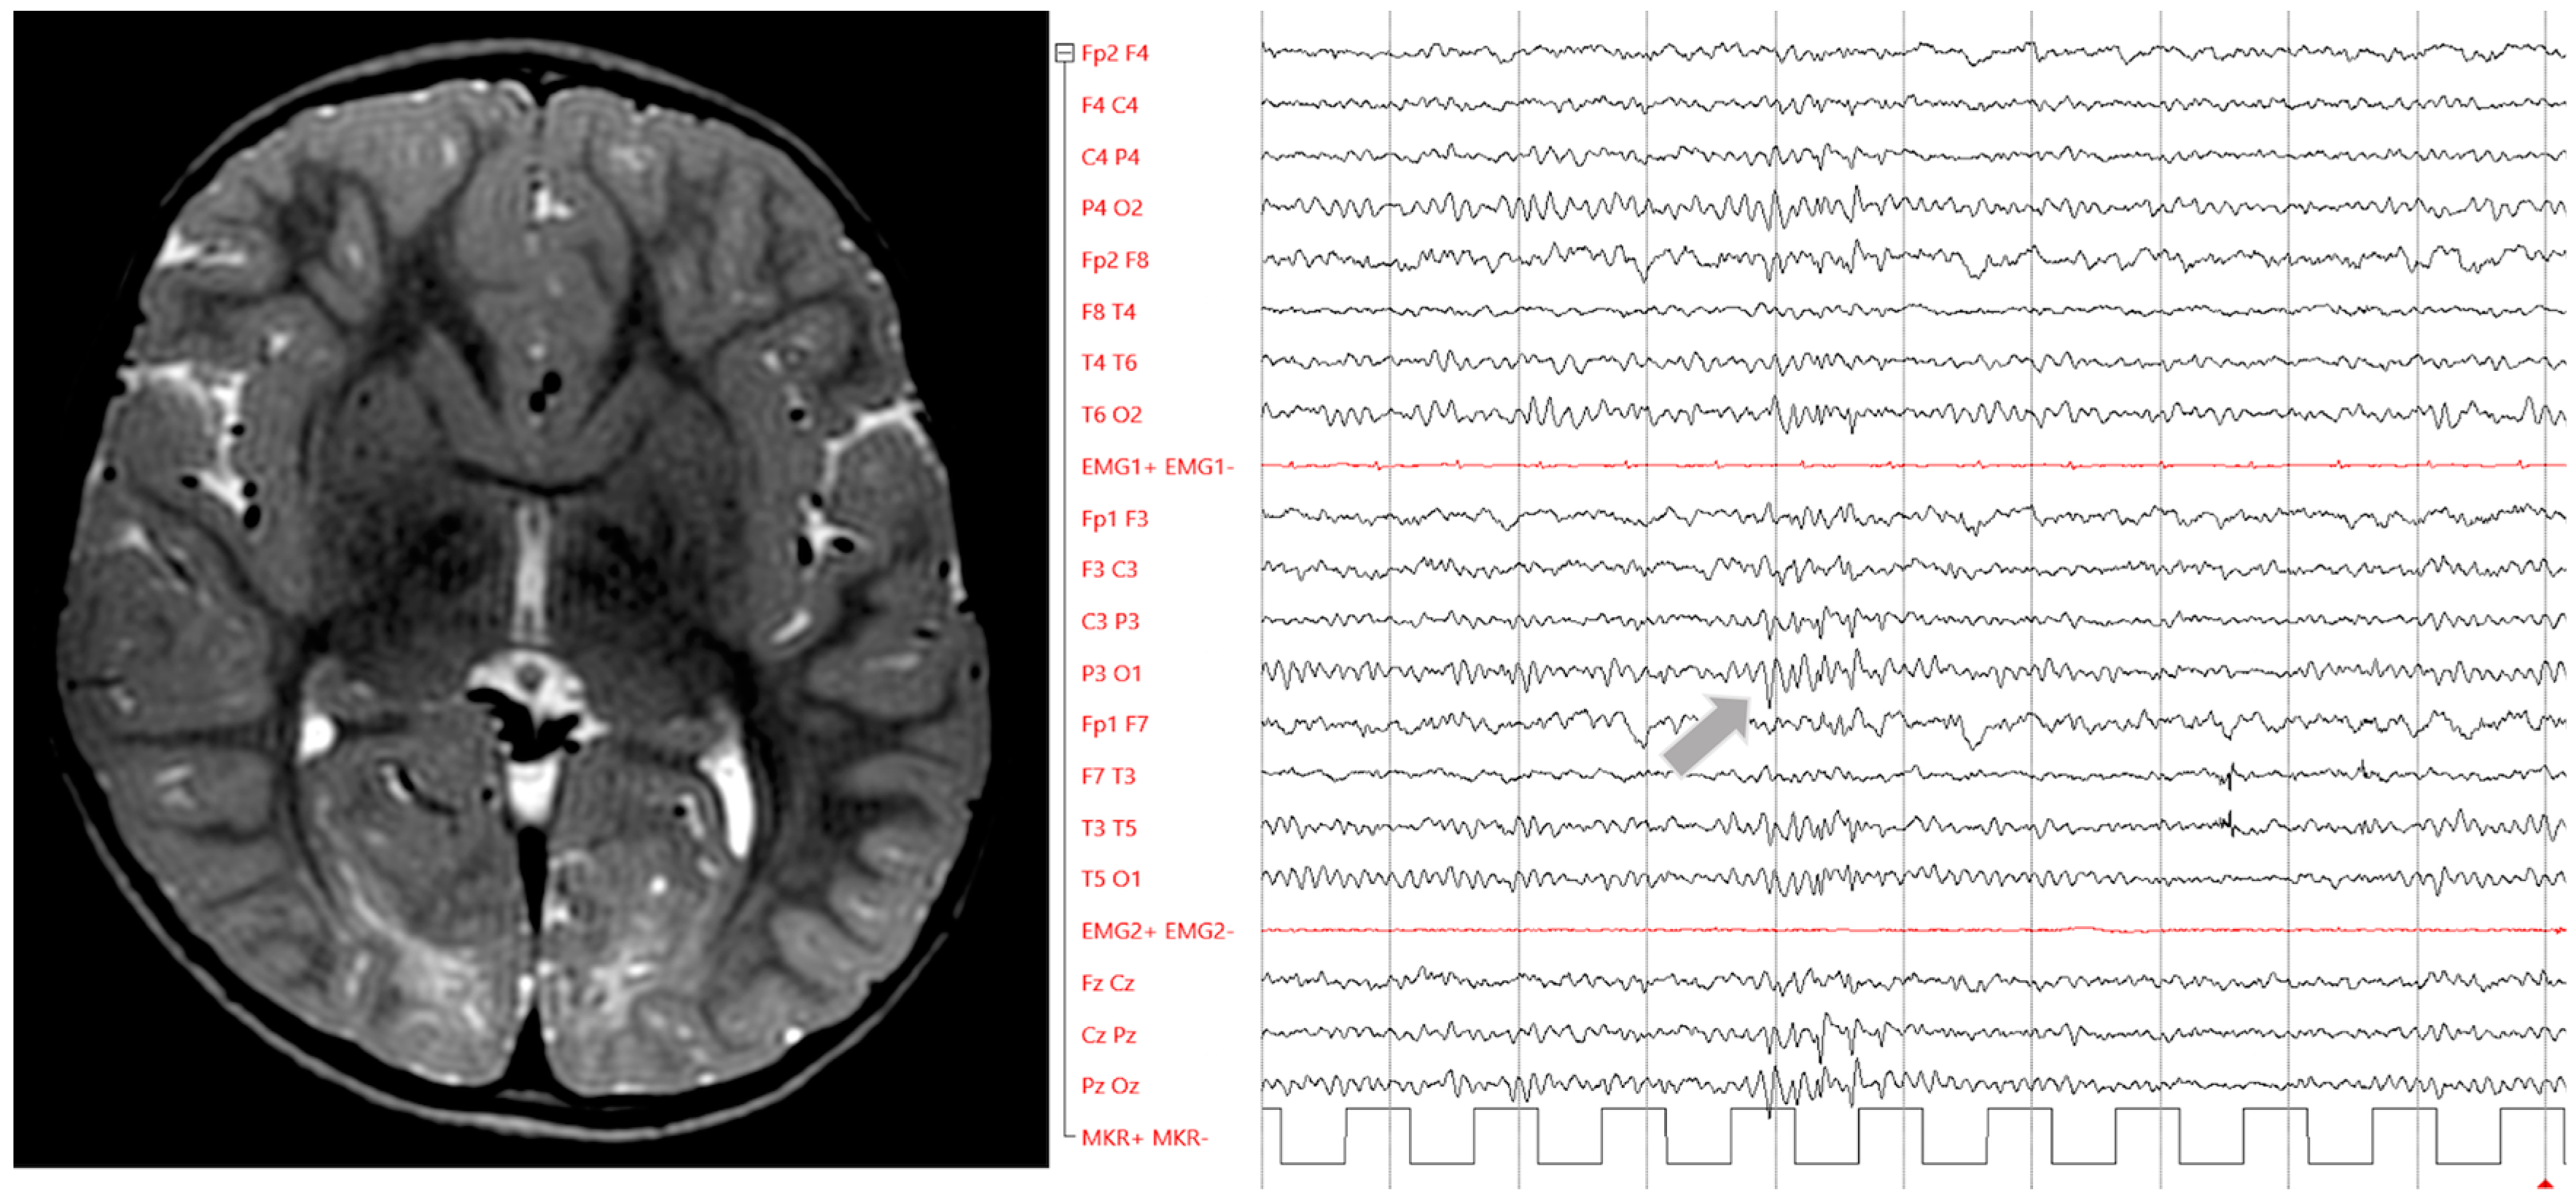

3.2.2. Hyperglycaemia in Older Children

- Bathla, G.; Policeni, B.; Agarwal, A. Neuroimaging in Patients with Abnormal Blood Glucose Levels. Am. J. Neuroradiol. 2014, 39, 833–840. [Google Scholar] [CrossRef]

- Moien-Afshari, F.; Téllez-Zenteno, J.F. Occipital seizures induced by hyperglycemia: A case report and review of literature. Seizure 2009, 18, 382–385. [Google Scholar] [CrossRef]

- Urbach, H.; Berger, B.; Solymosi, L.; Zimmermann, J. “Negative T2 shine through” in patients with hyperglycemia and seizures: A frequently overlooked MRI pattern. Neuroradiology 2020, 62, 895–899. [Google Scholar] [CrossRef]

- Çokar, Ö.; Aydın, B.; Özer, F. Non-ketotic hyperglycaemia presenting as epilepsia partialis continua. Seizure 2004, 13, 264–269. [Google Scholar] [CrossRef] [PubMed]

- Hung, W.-L.; Hsieh, P.F.; Lee, Y.-C.; Chang, M.-H. Occipital lobe seizures related to marked elevation of hemoglobin A1C: Report of two cases. Seizure 2010, 19, 359–362. [Google Scholar] [CrossRef] [PubMed]

- Raghavendra, S.; Ashalatha, R.; Thomas, S.V.; Kesavadas, C. Focal neuronal loss, reversible subcortical focal T2 hypointensity in seizures with a nonketotic hyperglycemic hyperosmolar state. Neuroradiology 2007, 49, 299–305. [Google Scholar] [CrossRef]